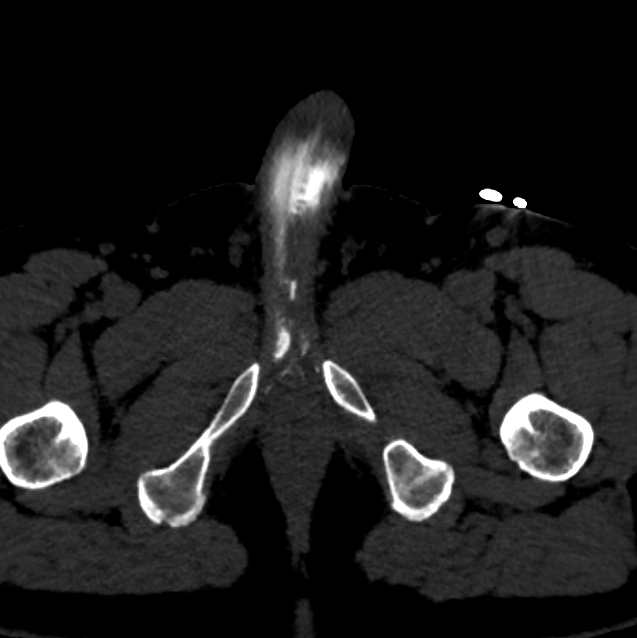

3. При венозной утечке уролог может отправить вас на абсолютно демоническую методику (которой в целом я и занималась) — КТ-кавернозографию. Однако, именно этот метод демонстрирует нам куда что утекает, и с какими сосудами будет работать сосудистый хирург. Хирург эмболизирует те сосуды, в которые происходит венозная утечка, таким образом на длительной время (пока не развились новые венозные коллатерали) обеспечит поддержание эрекции.